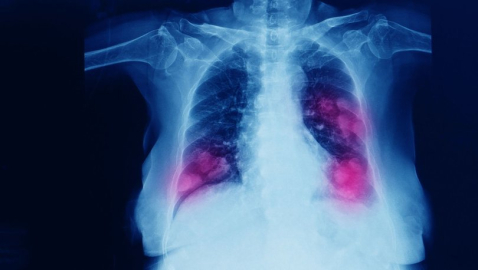

Tucumán Eyaleti Sağlık Bakanı Luis Medina Ruiz, gizemli pnömoniye (zatürre) yakalanan İlk 6 hastanın 18-22 Ağustos tarihleri arasında yoğun akciğer enfeksiyonu ile hastaneye başvurduklarıı ve nefes almada güçlük ve göğüs ağrısı benzeri semtomlar gösterdiklerini söyledi. Ruiz, “Bu hastaların ortak noktası, iki taraflı pnömoni ile şiddetli solunum rahatsızlığı ve Kovid-19’a çok benzeyen X-Ray görüntülerindeki benzerliktir.

Ancak, hastaların ‘Kovid-19, soğuk algınlığı, hem A hem de B tipi grip’ dahil olmak üzere 30’dan fazla virüs ve bakteri için test edilmiş ve bunların hepsi negatif çıkmıştır” dedi. Hastalardan alınan numunelerin daha fazla analiz için Arjantin Ulusal Sağlık Laboratuarları’na gönderildiğini belirten Ruiz, karantinaya alınan hastaların temas edenlerin de izlenerek izole edildiğini vurguladı.